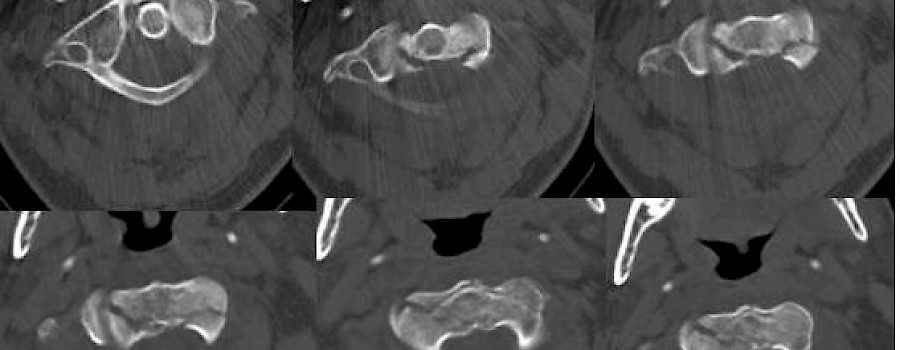

HWS - isolierte Knochenspange

Blockwirbelbildung HWK 5/6 - Deutliche Osteochondrosen in den angrenzenden Segmenten - Dorsal auffällige isolierte Knochenspange angrenzend an den Dornfortsatz HWK 6, am ehesten im Sinne einer

Patient kommt nach Verkehrsunfall mit Schleudertrauma zum Ausschluss einer knöchernen Verletzung!

Patient - männlich -54 Jahre alt ist im Bad ausgerutscht und mit dem Genick auf Badewannenrand geschlagen.